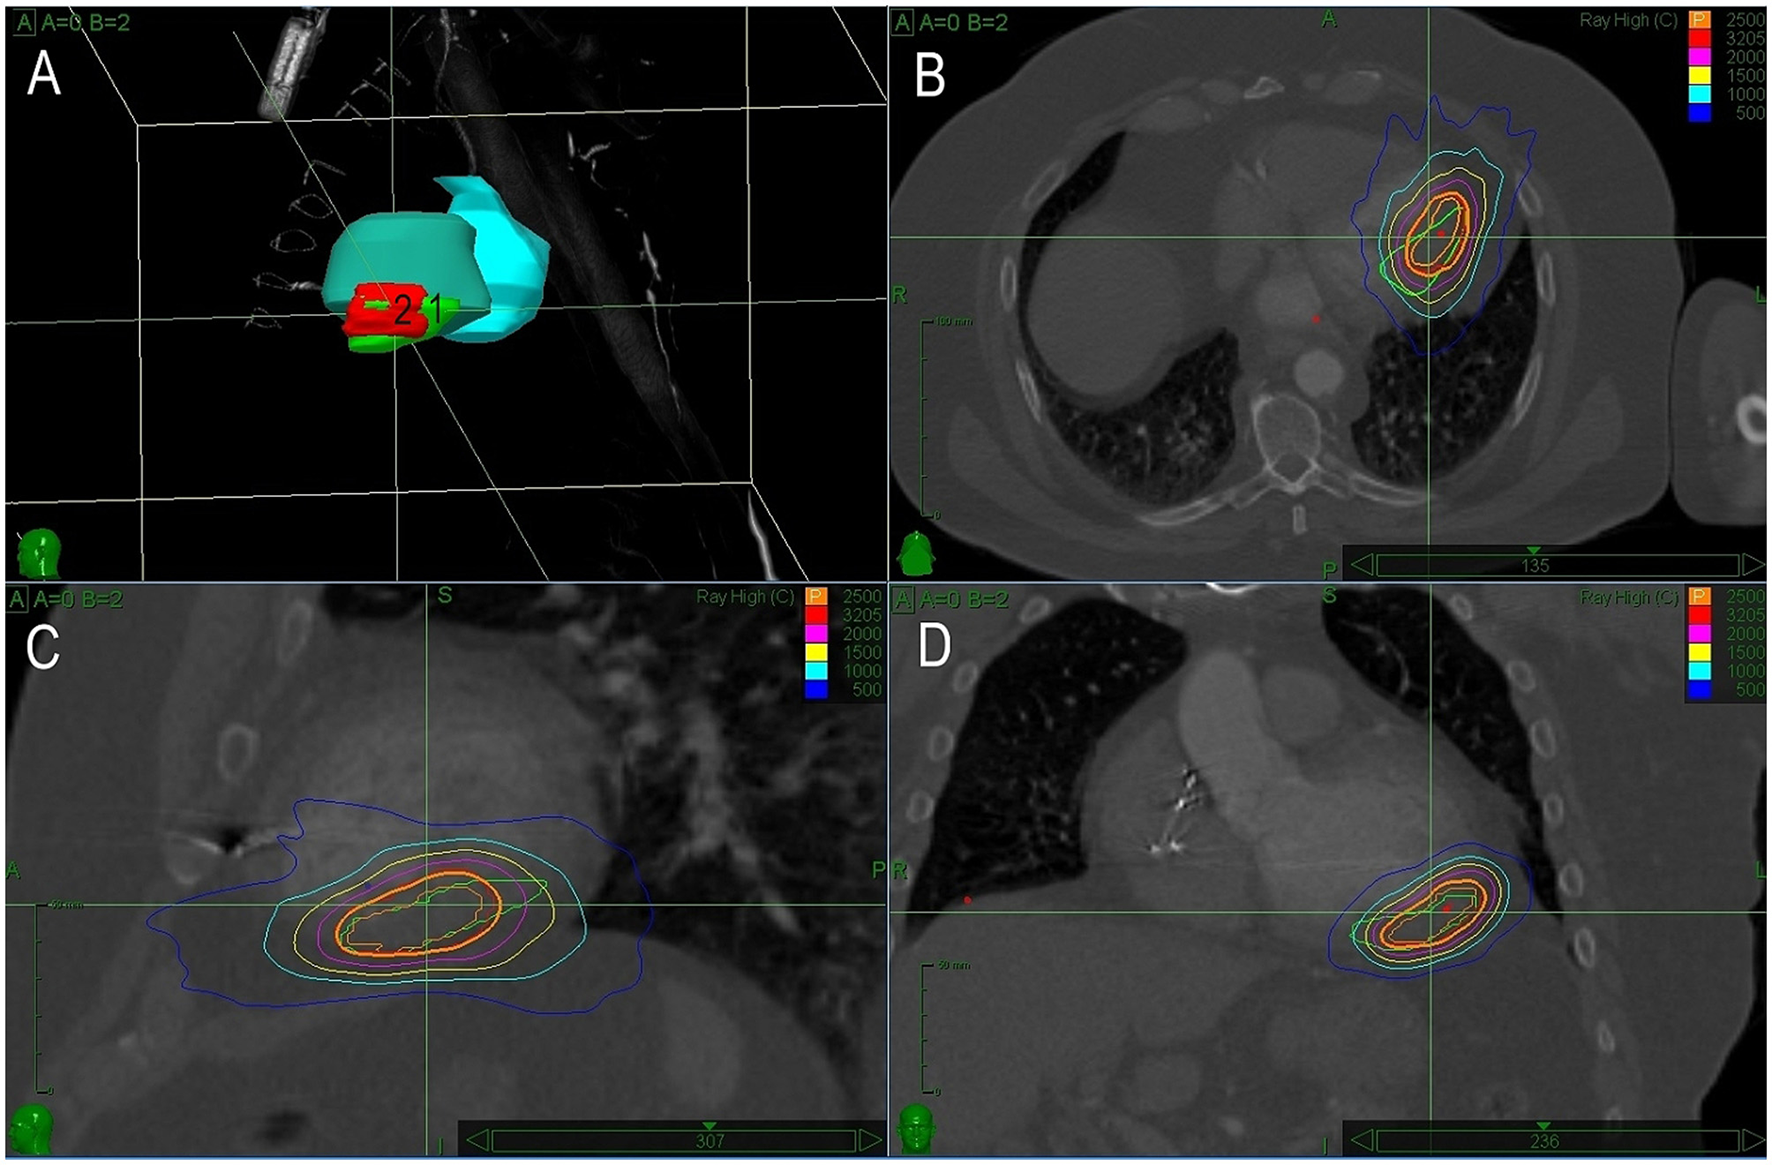

The first case was reported recently in detail as a case report, illustrating the need for precision in planned target volume (PTV) determination (20). Briefly, a 66-year-old man with a history of coronary artery bypass graft surgery and primary prophylactic ICD implant (left ventricular ejection fraction of 35%) underwent catheter ablation for recurrences of slow VT. Clinical VT originated from a small reentrant circuit located intramurally and/or epicardially below the base of the posteromedial papillary muscle. Despite multiple endocardial ablation attempts, VT remained inducible and an attempt for percutaneous epicardial approach failed because of severe adhesions from previous cardiac surgery. The first SBRT session was planned based on a visual alignment of the presumed origin of VT from electroanatomical maps and CT images. A single fraction of 25Gy was delivered. For recurrences of VT episodes of the same ECG morphology, the patient underwent the second electrophysiology study and remapping 14 months later. Based on the electroanatomical mapping, the low voltage area caused by the previous SBRT was adjacent to the site of the earliest endocardial activity during VT. Additional RF ablation failed again to prevent the inducibility of VT and we used a newly developed co-registration method for the precise targeting of the SBR (20). Detailed maps were presented in a previously published case report (20). Briefly, there was only a small bipolar low voltage area after the first SBRT which was adjacent to the true exit of VT. Precise co-registration of the target in the second SBRT allowed to establish a smaller PTV amounting to 18 ml, including an additional 3 mm margin. The dice overlap of previous and new PTV was 0.68. The second session was performed 19 months after the first one. The same dose of 25 Gy was delivered (Figure 1). After transient early recurrences of slow VT, arrhythmias gradually disappeared within 3 months and the patient became arrhythmia-free for 32 months. No adverse effect of SBRT was observed during this period.

Figure 1

A treatment plan for Case 1. (A) 3D reconstruction of planned treatment volumes for the first (1) and second (2) radiotherapy. (B–D) Depict sagittal, coronal, and axial views with isodose lines for both sessions of radiotherapy (green line shows target volume for the first and red for the second session). In this case, there is a significant overlap of both treatment volumes caused by inaccuracy in the planning of the first session.